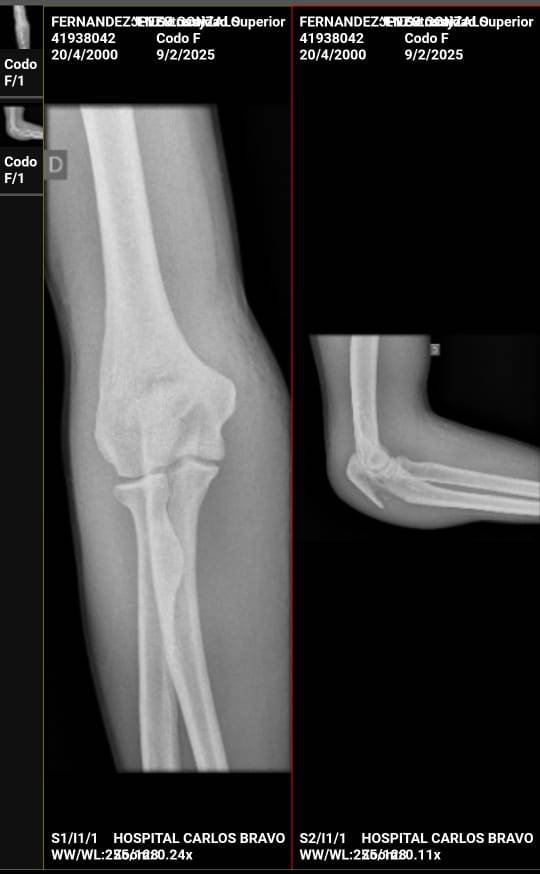

Ahora, se ha confirmado que Fernández sufrió una fractura del cubito y radio del antebrazo derecho, lo que requiere una intervención quirúrgica urgente y la instalación de una prótesis. Esta lesión lo mantendrá alejado de la cancha por varios meses.